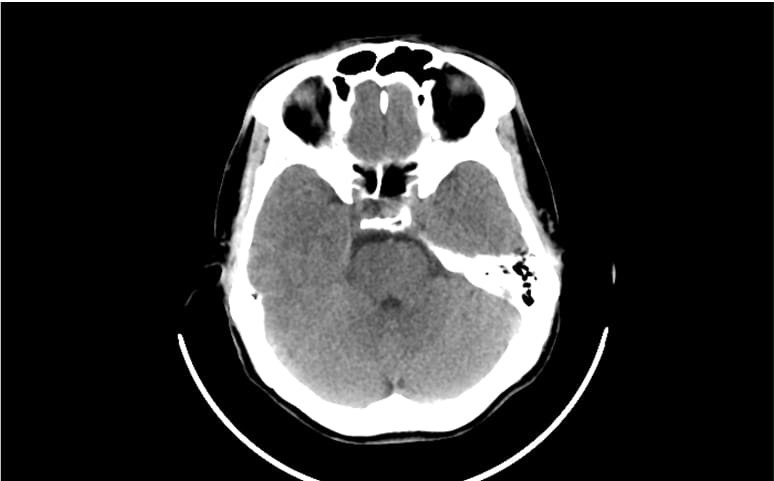

- 9% decrease in CTB reporting time in real world clinical practice.¹

Facilitate accurate diagnoses of complex and subtle cases with AI-decision support identifying up to 124 findings on CXR and 130 findings on CTB.

- Detect up to 39 critical and 42 urgent findings on head CT.

- AI results are available within 20 seconds for CXR or 90 seconds for CTB.

Look beyond a single point solution. Unlock 100+ clinical findings with comprehensive AI solutions for CXR and head CT.

- Some of the world’s most comprehensive radiology AI solutions for CXR (124 findings) and CT Brain (130 findings).